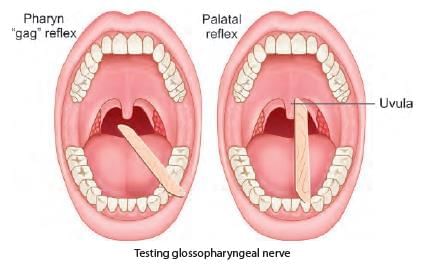

A patient was admitted with skull base trauma and difficulty in swallowing. The doctor was touching the marked structure. Which of the following cranial nerve is being tested? (NEET-PG 2021)